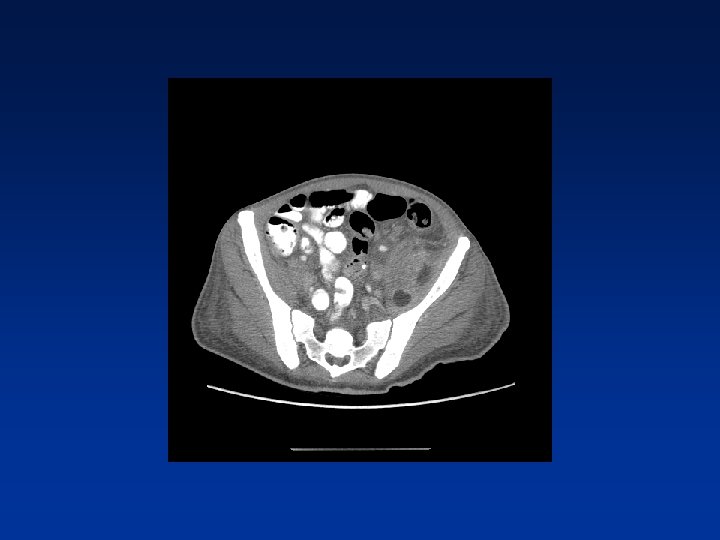

CASE